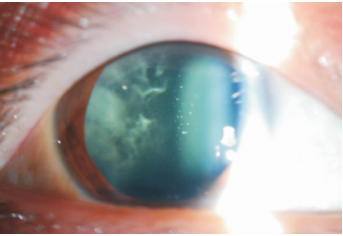

患者男性,44 岁。因“双眼先后出现黑影飘动3 年,加重 1 年”来我院就诊。全身检查无特殊,入院常规检查均无异常。患者之母,两个姨妈,一个舅父及外婆均为中年发病,双眼玻璃体混浊,其中两人于当地医院已行玻璃体切除, 一人术后继发青光眼。眼部检查: 视力右眼指数 /10 cm,左眼0.3,矫正均无提高。双眼眼压均为 13.5 mmHg(1 mmHg= 0.133 KPa) 。双眼眼前节无特殊, 玻璃体呈白色致密混浊, 其中间杂高密度白色混浊点。颗粒状白色混浊部分呈“足盘”样粘附于晶状体后囊膜(图1) 。视网膜模糊, 隐约可见周边视网膜小血管表面有棉绒斑样白色渗出。UBM 检查无异常, B 超显示玻璃体混浊,部分后脱离声像。

图 1 患者术前右眼眼前段彩照,前段玻璃体棉絮样混浊,“足盘”状白色颗粒附着于晶状体后囊膜